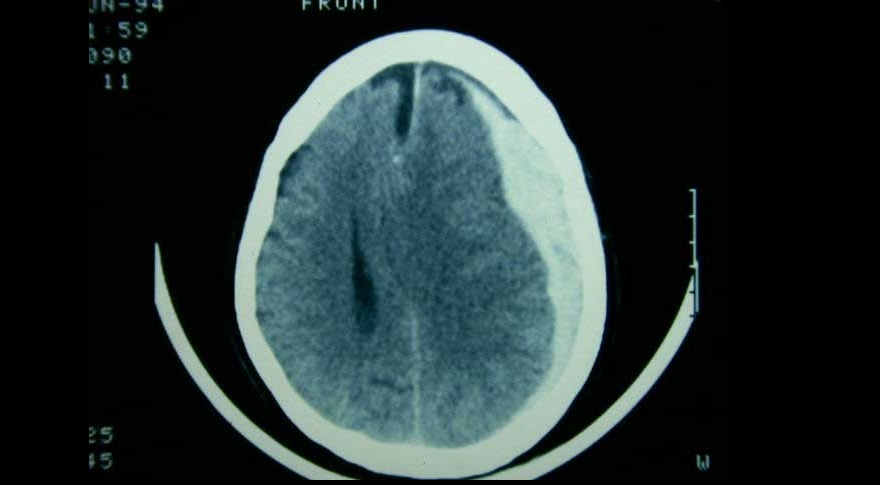

Embolización de la arteria meníngea media en el hematoma subdural subagudo o crónico

21 noviembre 2024

Tres ensayos clínicos exploran la utilidad de la embolización de esta arteria en el manejo del hematoma subdural subagudo o crónico, con miras a reducir la tasa de recurrencias y la necesidad de nuevas intervenciones. New England Journal of Medicine, 20 de noviembre de 2024.